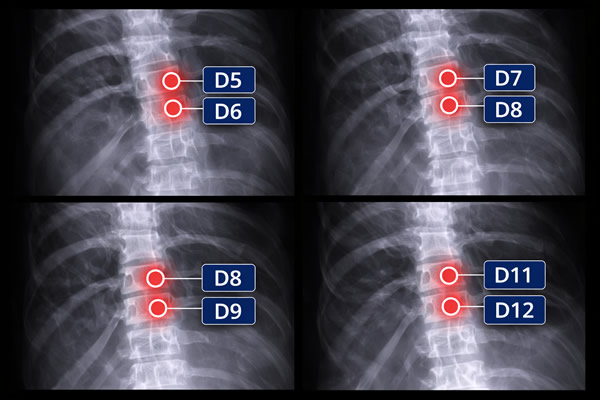

D5, D6, D7, D8, D9, D11 y D12 son vértebras dorsales (la parte media de la espalda). Cuando una hernia se describe como D5–D6, D7–D8, D8–D9 o D11–D12, significa que el problema está en el disco situado entre esas vértebras, justo en esta zona del tronco. Aunque las hernias dorsales son menos frecuentes que las cervicales o lumbares, pueden provocar dolor en la espalda, rigidez y molestias que a veces rodean el pecho o se notan alrededor de las costillas.

En ese nivel, el disco puede protruir o herniarse hacia atrás y irritar/comprimir nervios cercanos o, en los casos más delicados, afectar estructuras del canal medular. Lo importante es entender que “D5–D6 / D7–D8 / D8–D9 / D11–D12” no es solo una forma de nombrarla: indica dónde está el origen del problema y por qué, desde esa zona dorsal, pueden aparecer síntomas que no siempre se quedan solo en la espalda.